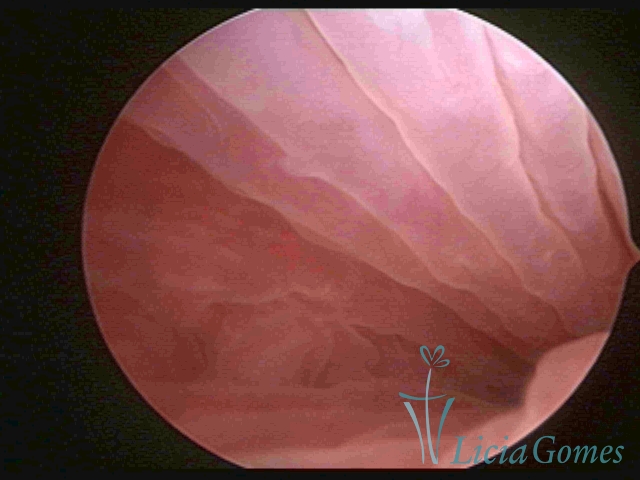

Third part or upper section

Presents the mucosa with a smooth, poorly vascularized surface, to the internal orifice